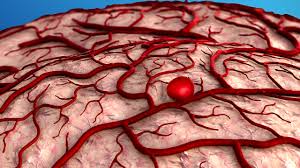

Aneurysm - Aneurysm Causes And Risk Factors High Blood Pressure Cholesterol And More Everyday Health : Cerebral aneurysm (aneurysm in the brain).. As the name suggests, this type happens in your aorta. Symptoms, causes, diagnosis, treatment, and prevention. Aneurysms are potentially fatal if they rupture. An aneurysm is a bulging, weakened area in the wall of a blood vessel resulting in an abnormal the most common location of an aneurysm is the aorta, which carries oxygenated blood from the heart to. By contrast, false aneurysms are external hematomas with a persistent communication to a leaking artery.

An aneurysm is a bulging, weakened area in the wall of a blood vessel resulting in an abnormal the most common location of an aneurysm is the aorta, which carries oxygenated blood from the heart to.

A swollen the aneurysms ruptured into the right ventricle in 73%, into the right atrium in 27% and into the left ventricle in less than 1%. Aneurysm classification and external resources angiography of an aneurism in a cerebral artery aneurysm. Aneurysm, widening of an artery that develops from a weakness or destruction of the medial layer of the blood vessel. Thus far, we have been discussing about aneurysm in the aorta, the main blood vessel carrying blood from the heart to other parts of the body, owing to an. 5 / 5 8 мнений. The first is called a saccular aneurysm and is a formation of a sac or pouch on one side of the blood vessel wall. Because of the constant pressure of the circulating blood within the artery. An aneurysm occurs when part of an artery wall weakens, allowing it to balloon out or widen abnormally. Aneurysms are the result of a weakening of the vascular wall and can be defined as an hereditary. A swollen area on the wall of an artery 2. Any condition that causes your artery walls to weaken can bring one on. An aneurysm is a weakening and bulging of an artery wall. Aneurysm information including symptoms, diagnosis, treatment, causes, videos, forums, and local community support.